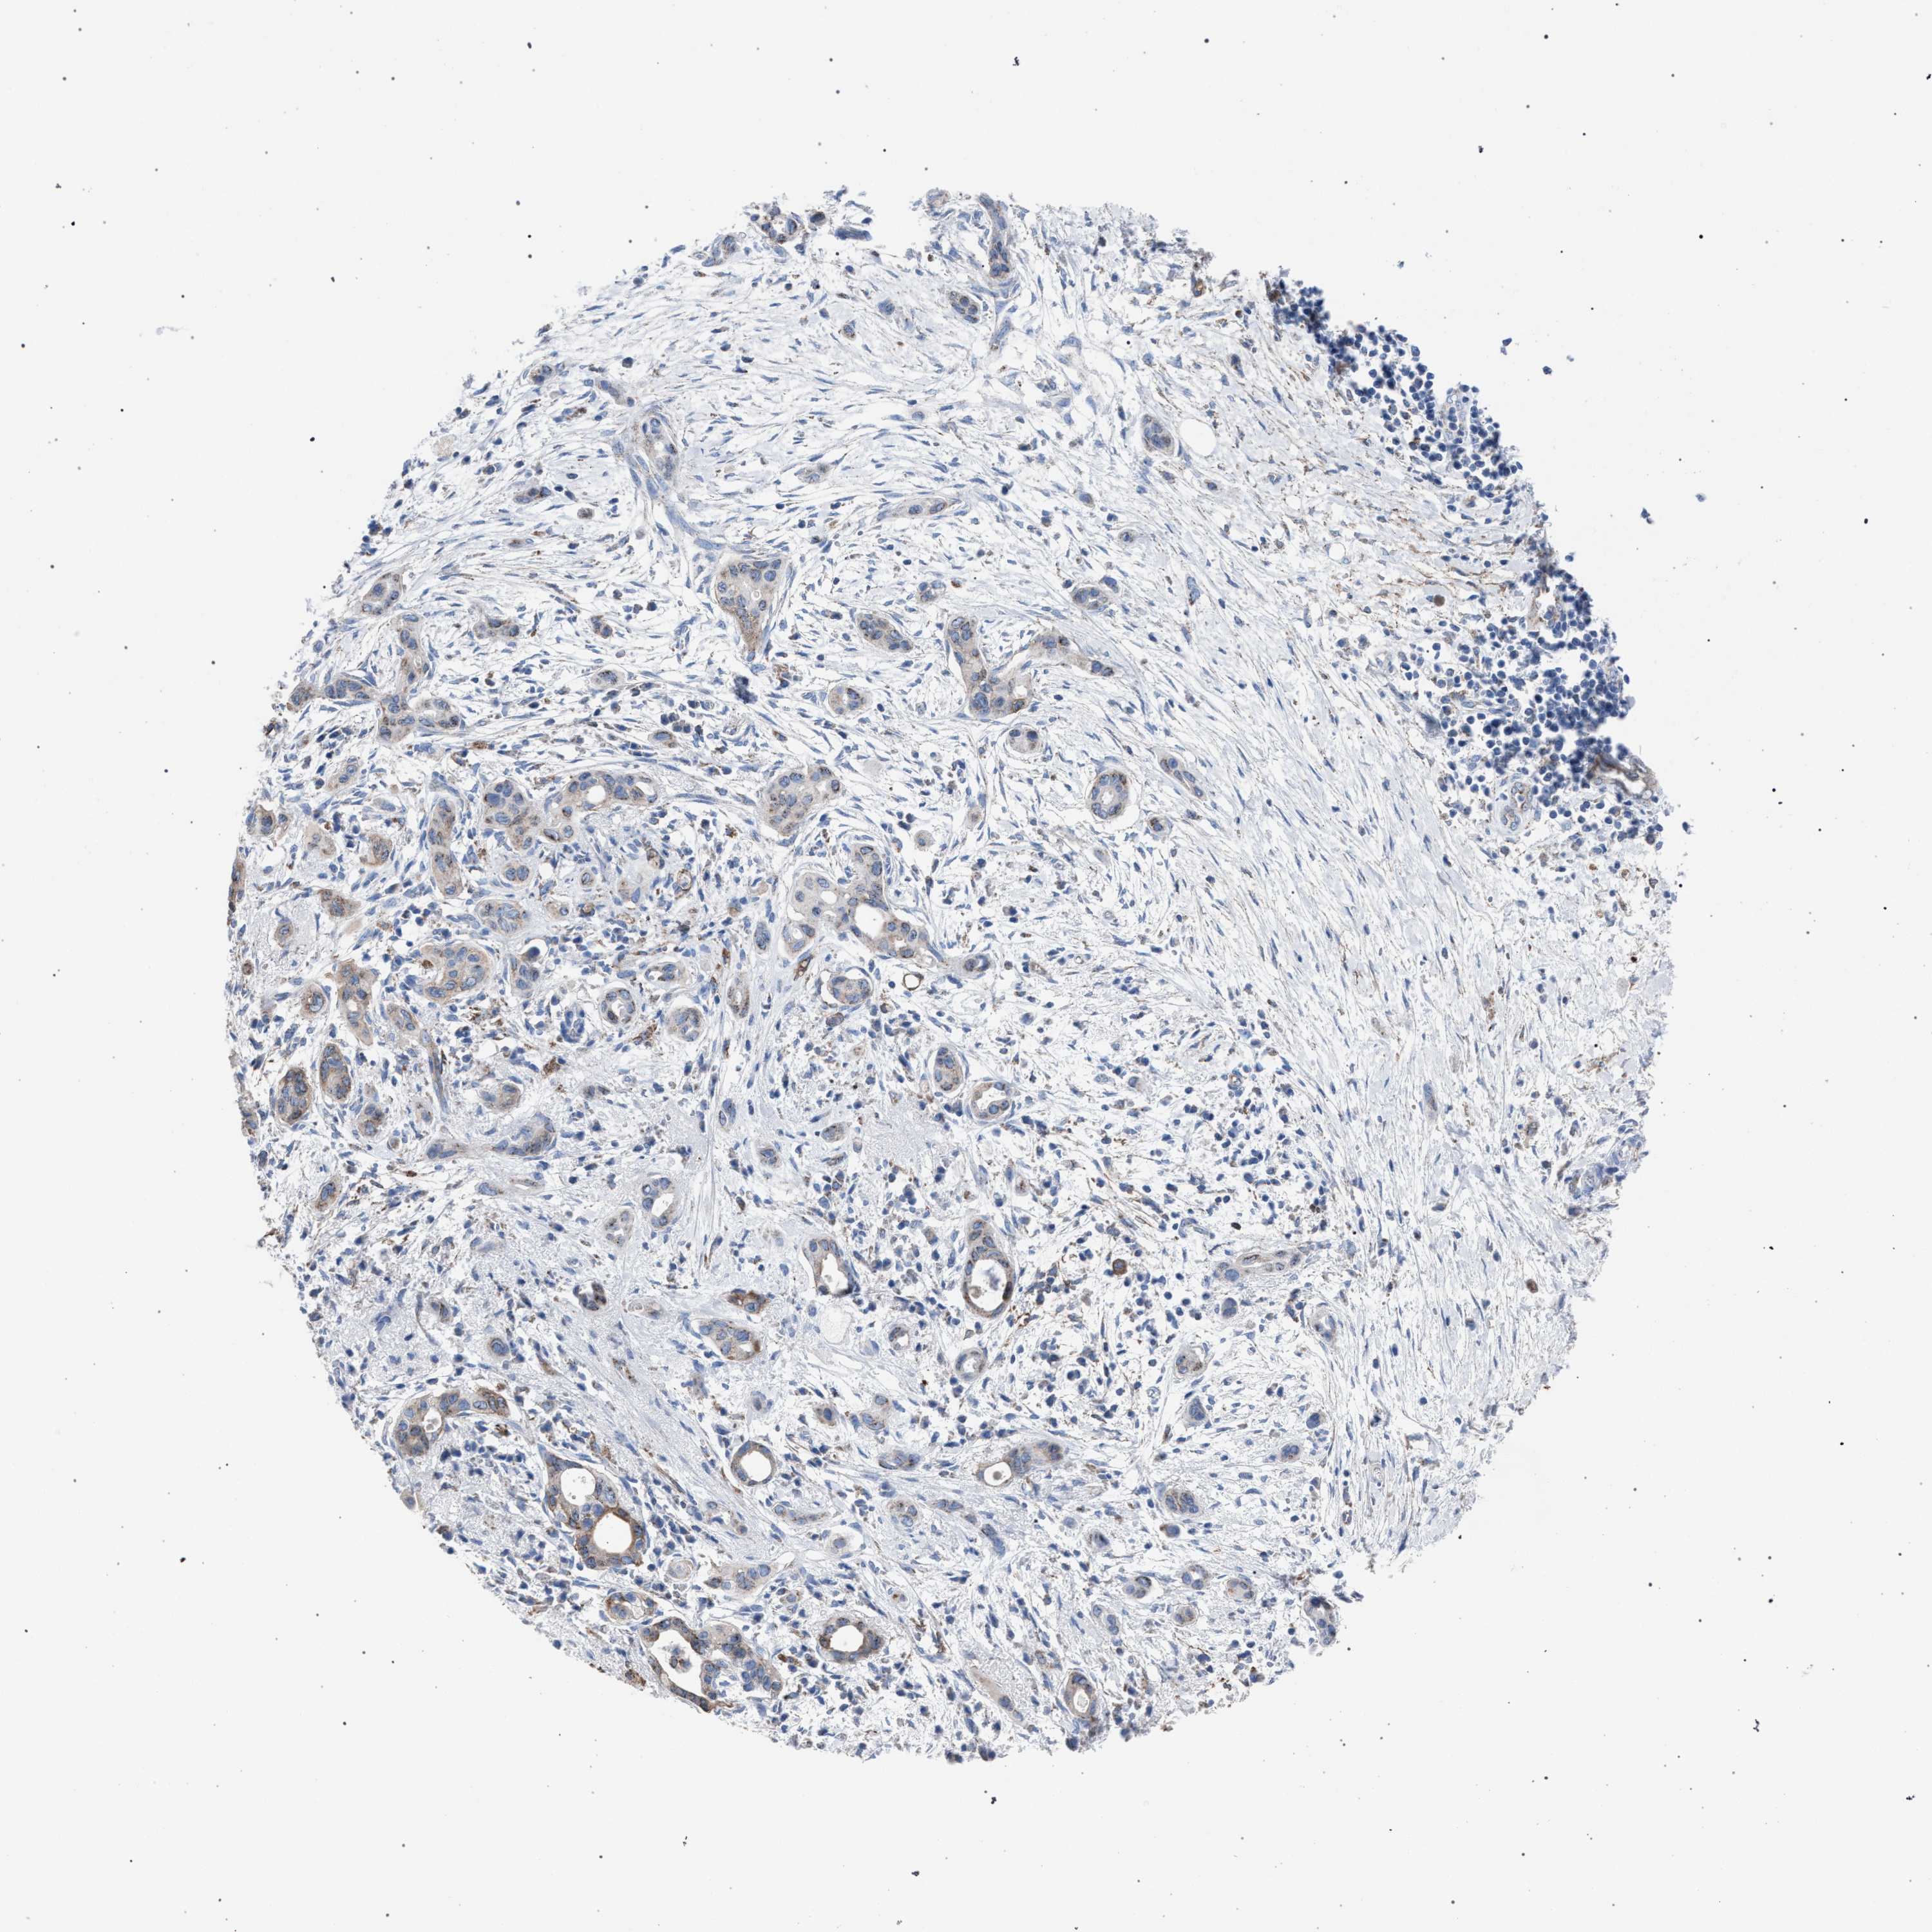

PANCREATIC CANCER - Protein expressioni

A mouse-over function shows sample information and annotation data. Click on an image to view it in a full screen mode. Samples can be filtered based on level of antibody staining by selecting one or several of the following categories: high, medium, low and not detected. The assay and annotation is described here.

Note that samples used for immunohistochemistry by the Human Protein Atlas do not correspond to samples in the TCGA dataset.

Antibody stainingi

Antibody staining in the annotated cell types in the current human tissue is reported as not detected, low, medium, or high, based on conventional immunohistochemistry profiling in selected tissues. This score is based on the combination of the staining intensity and fraction of stained cells.

Each image is clickable and will lead to virtual microscopy that enables deeper exploration of all samples and also displays staining intensity scores, fraction scores and subcellular localization as well as patient and tissue information for each sample.

Antibody HPA021302

Antibody HPA021311

Antibody HPA021479

Staining

High

Medium

Low

Not detected

Intensity

Strong

Moderate

Weak

Negative

Quantity

>75%

75%-25%

<25%

None

Location

Nuclear

Cytoplasmic/membranous

Cytoplasmic/membranous,nuclear

Adenocarcinoma, NOS